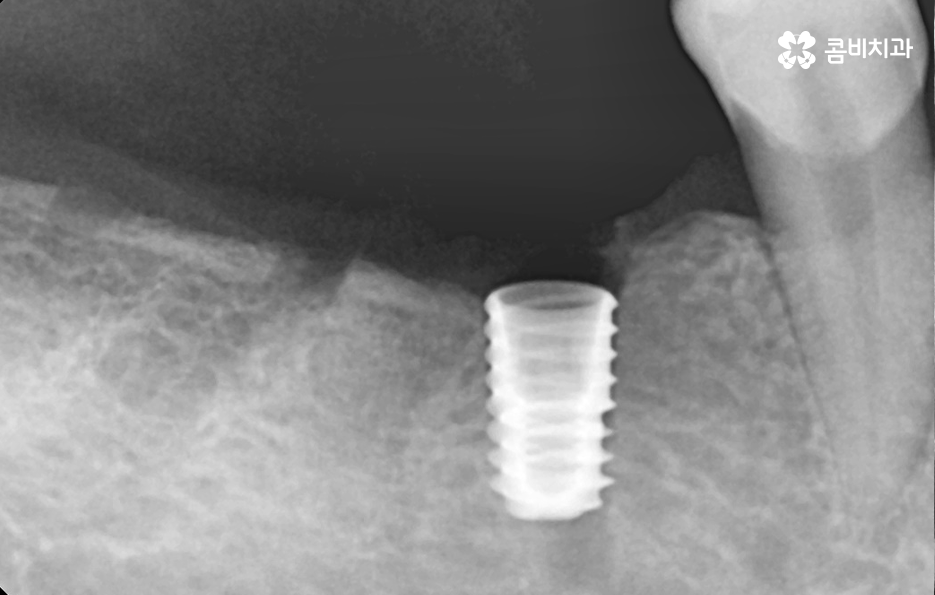

반면에 치주염이 심해져서 치조골이 녹아내리고 이미 치아의 뿌리가 보일 정도로 잇몸이 약해진 상태에는 치아 발치 후 잇몸이 충분히 회복한 뒤 임플란트를 식립할 수 있는 잇몸 뼈가 충분한지 확인 후 경우에 따라서는 뼈이식이 추가될 수 있는데요.

임플란트는 잇몸 뼈에 식립하기 때문에 치주염으로 인해 잇몸 뼈가 부족하거나 치아를 발치 후 오랜 시간이 지난 다음에 임플란트를 하게 될 경우 임플란트를 식립할 충분한 잇몸 뼈의 확보를 위해 뼈이식을 받아야 할 수 있어요

쉽게 생각하면 임플란트는 인공치근으로도 불리고 있는데 치아의 뿌리를 대신하여 임플란트가 잇몸 뼈에 식립되고 골유착 과정을 통해 단단하게 고정되어 저작력을 얻고 있는데요